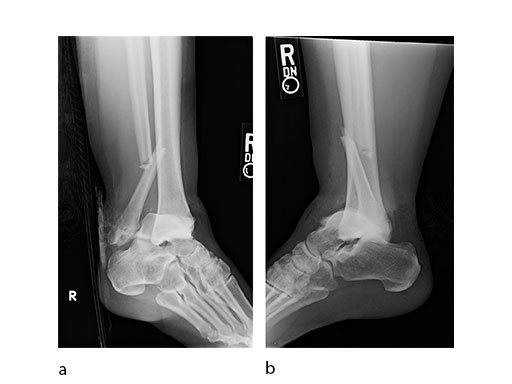

Case 2: Scaffolding fall (Case provided by Mark Lee, Sacramento, USA)

A 61-year-old laborer fell 5 meters from scaffolding. This was a closed injury with severe soft-tissue injury (Fig 67). He required three weeks of jointspanning external fixation prior to adequate resolution of edema.

Initial fixation was via a limited posteromedial exposure to buttress a posteromedial partial articular fragment (Fig 8). Following articular reduction and supplemental lateral column plate fixation via a limited anteromedial joint exposure, the VA-LCP Anteromedial Distal Tibia Plate was passed subcutaneous with subsequent percutaneous screw insertions into the plate shaft.

There was good maintenance of reduction at 5 weeks (Fig 9).